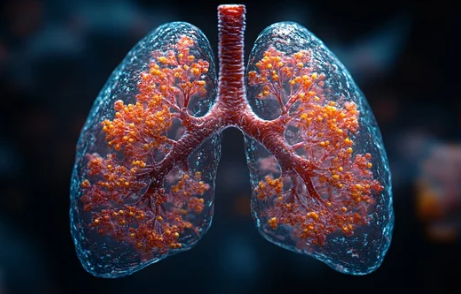

폐섬유화는 폐 조직이 점진적으로 딱딱해지며 호흡 곤란을 유발하는 질환으로, 조기 발견과 적절한 관리는 매우 중요합니다. 이 글에서는 폐섬유화의 주요 증상, 원인, 치료 방법에 대해 폭넓게 살펴보겠습니다. 또한 관련 정보를 제공하는 사이트와 최신 연구 동향도 함께 안내합니다.

폐섬유화는 폐 조직에 섬유화(흉터 조직)가 발생하여 정상적인 폐 기능이 점점 상실되는 질환입니다. 이는 산소와 이산화탄소의 교환을 방해해 호흡에 큰 어려움을 초래할 수 있습니다.